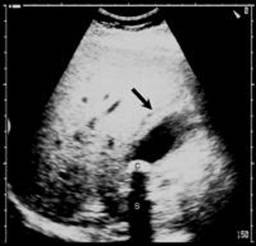

L'ecotomografia è quasi da sempre indagine di prima istanza nello studio della patologia infiammatoria della colecisti, per la semplicità di esecuzione e i bassissimi costi. L'esame è effettuato a paziente inizialmente in decubito supino, con approccio sottocostale, in inspirazione profonda per poter utilizzare la finestra acustica epatica, e successivamente in decubito obliquo posteriore sinistro, con approccio intercostale, in espirazione profonda per allontanare l'aria dai seni costo diaframmatici. Si eseguono scansioni longitudinali e trasversali rispetto all'asse principale della colecisti.

I criteri morfologici ultrasuonografici tipici di colecistite acuta possono essere classificati in maggiori e minori.

Tra i maggiori:

- Calcoli in sede colecistica (presenti in più del 90% dei pazienti);

1) Spessore della parte colecistica di più di 3mm;

2) Fluido pericolecistico (segno di una attuale o imminente perforazione d'organo);

3)Slaminamento della parete (indicativo di edema infiammatorio);

4) Positività al segno ecografico di Murphy (dolore slatentizzato alla compressione della colecisti attraverso la sonda ecografica);

5) Gas intramurale (segno indicativo di colecistica enfisematosa);

I criteri minori

includono la presenza di sludge biliare nella colecisti e un aumento del suo

diametro trasverso di più di

Per confermare la diagnosi di colecistite acuta è necessaria la presenza di due criteri maggiori oppure uno maggiore e due minori.

La diagnosi della colecistite acuta è rapida, non invasiva, facilmente eseguibile e molto sensibile, anche se purtroppo, operatore dipendente.

La sensibilità e la specificità dell'esame ultrasonografico nella colecistite acuta sono rispettivamente dell'81-100% e del 60-100%. 13 ,14

Fig 3 Esame ultrasonografico dell'addome . slaminamento della parete colecistica

Fig 4 Esame ultrasonografico dell'addome . slaminamento della parete colecistica